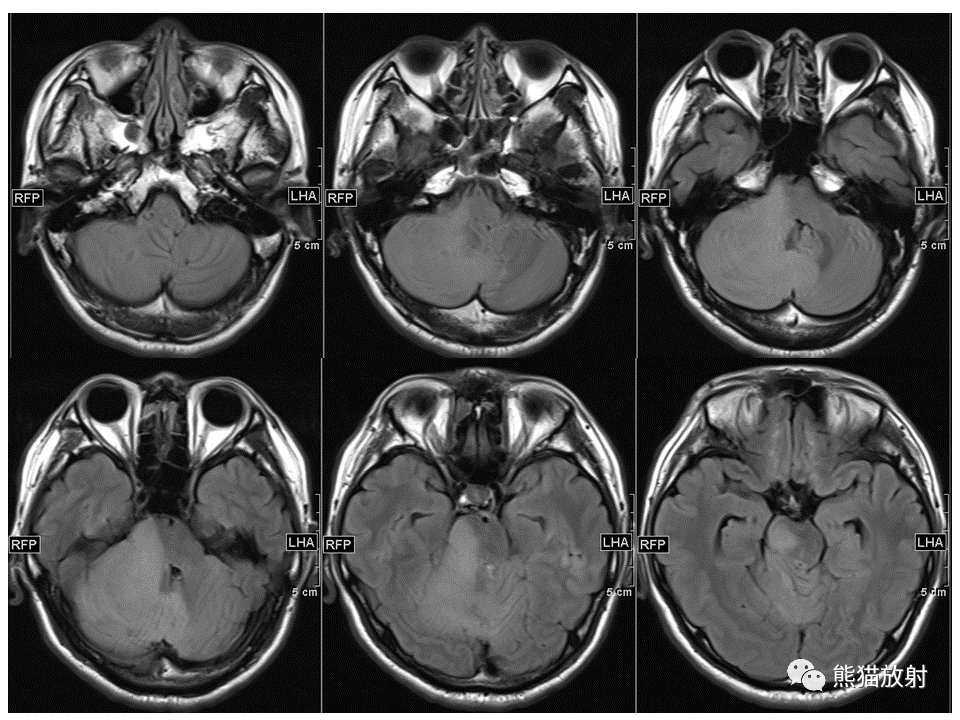

【PPT】小脑发育不良性神经节细胞瘤 VS 成人型髓母细胞瘤-1